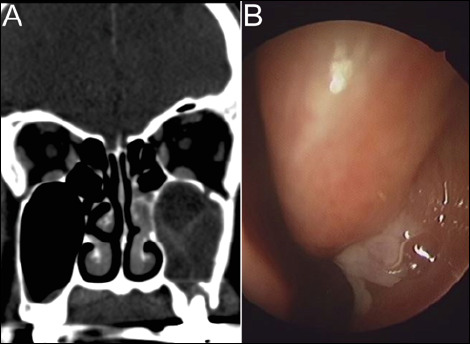

Objectives: To investigate the clinical efficacy of dental treatment and endoscopic sinus surgery (ESS), each primary/combined treatment modality, in patients with odontogenic sinusitis (ODS), according to its phase, acute or chronic.

Materials and methods: We retrospectively reviewed clinical data on 172 patients diagnosed with ODS. They were divided into two groups: acute (≤ 3 months; 90 patients) and chronic (> 3 months; 82 patients) ODS. The success rate and time to resolution of each primary/combined treatment modality were compared between the two groups.